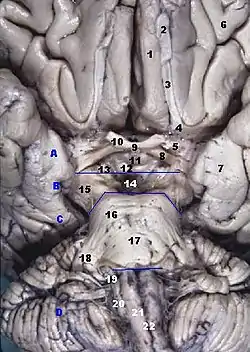

Human brainstem anterior view. Straight gyrus is numbered as #1 | |

The portion of the inferior frontal lobe immediately adjacent to the longitudinal fissure (and medial to the medial orbital gyrus and olfactory tract) is named the straight gyrus,(or gyrus rectus) and is continuous with the superior frontal gyrus on the medial surface.